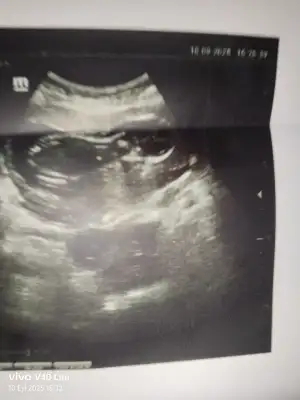

Merhaba 15 haftalık hala net bir şey söylemedi kız gibi diyor size atmak istedim sizce nedir